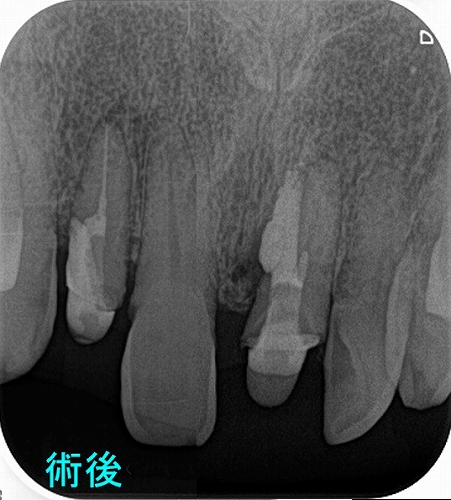

先日、治療した歯の調子がわるいという患者さん

ん~、水酸化カルシュウムが歯の外に押し出しているように見えます。

私はこの歯歯根破折だと判断し、抜歯させてもらいましたが。

抜いた歯には根尖病変内に水酸化カルシュウム